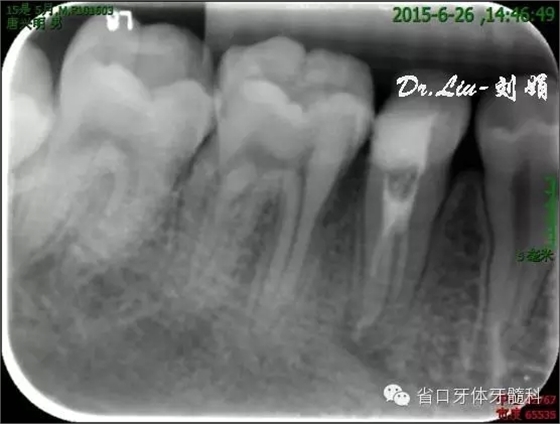

圖8:1月后復(fù)診根尖低密度影有消退趨勢(shì)

圖10:根充后X線片